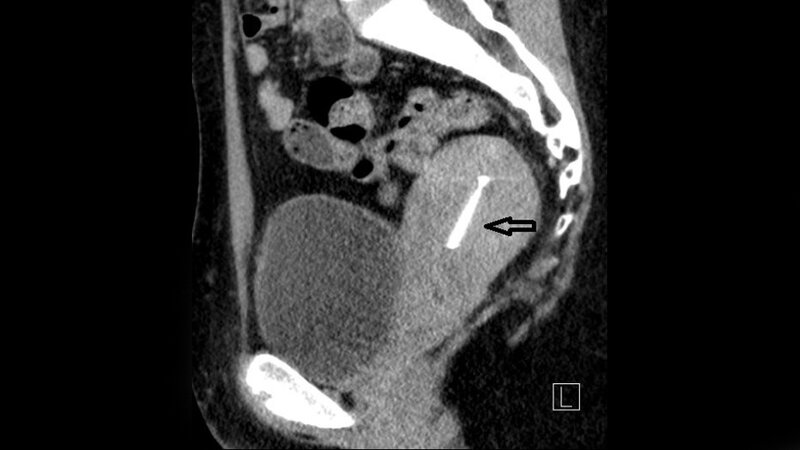

Schlüsselwörter: CT, MRT, Becken, Uterus, Retroflexio

Keywords: CT, MRI, pelvis, uterus, retroflexio